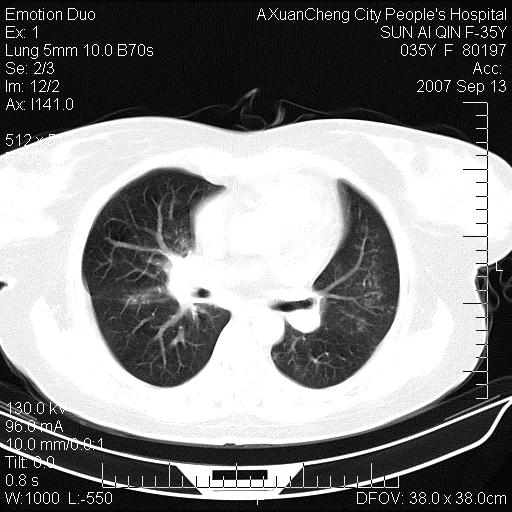

以下是引用天南地北在2007-9-13 13:43:00的发言:[br]考虑双肺、肺门侵润

以下是引用ydx_74在2007-9-13 15:42:00的发言:[br]仅看片,考虑右上肺癌并双肺转移,结合病史,考虑肺门、肺内淋巴侵润

以下是引用同在2007-9-13 15:08:00的发言:[br]支持肺门及双肺侵润.